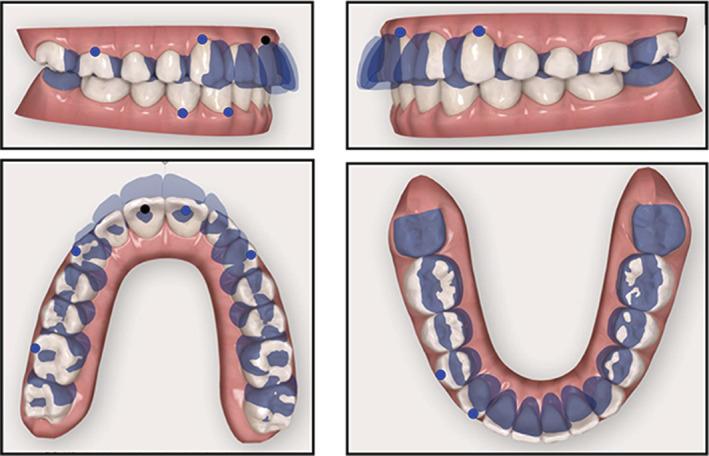

To describe an esthetic orthodontic treatment using aligners in an adult patient with dental class II malocclusion associated with crowding. A 25-year-old female patient with skeletal class I, bilateral class II relation, increased overjet and overbite and crowding in both arches presented for orthodontic treatment. The patient refused conventional fixed multibracket treatment in favor of aligners. Pre- and post-treatment records are presented. Treatment objectives were achieved in 10 months, and the patient was satisfied with the functional and esthetic outcomes. Combining aligners with appropriate attachment location and geometry is an efficacious means of resolving orthodontic issues such as class II malocclusion in a time frame comparable to that of conventional fixed orthodontics. Staging in distalization increases the predictability of movement. Furthermore, this system is associated with optimal oral hygiene and excellent esthetics.

描述在一名患有伴有牙列拥挤的安氏II类错牙合的成年患者中使用隐形矫治器进行的美学正畸治疗。一名25岁女性患者,骨骼I类,双侧安氏II类关系,覆盖和覆牙合增加,上下牙弓均有拥挤,前来接受正畸治疗。患者拒绝传统的固定多托槽治疗而选择隐形矫治器。展示了治疗前和治疗后的记录。在10个月内实现了治疗目标,患者对功能和美学效果感到满意。将隐形矫治器与合适的附件位置和几何形状相结合,是在与传统固定正畸相当的时间范围内解决诸如安氏II类错牙合等正畸问题的有效方法。远中移动分阶段进行可提高移动的可预测性。此外,该系统有助于保持最佳的口腔卫生并具有出色的美学效果。